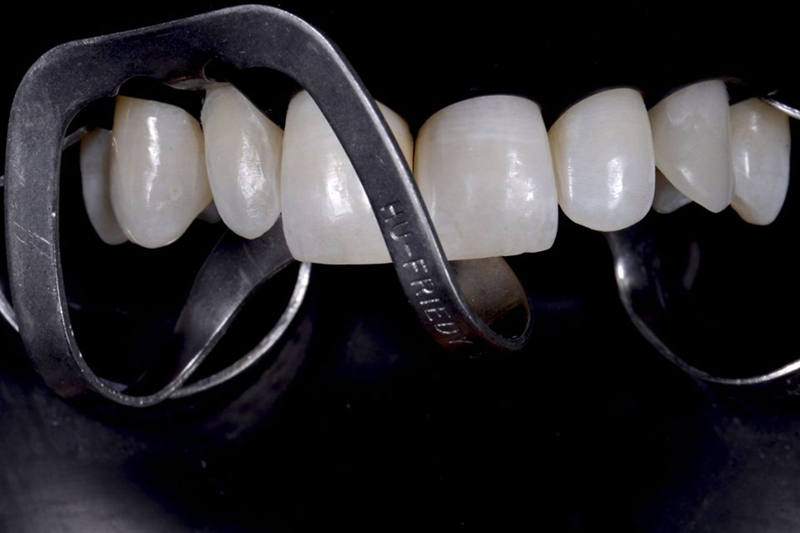

然后,对前庭侧陶瓷铣削后待贴面的氧化锆牙冠进行造型。一旦完成此步骤,就以此为参考生产氧化锆牙冠(图51)。铣削氧化锆牙冠和陶瓷贴面后,使用复合水泥将牙冠固定在 Variobase® 上(图 52)。然后,对最终的牙冠进行仔细抛光并调整以适应患者口腔中的位置(图53-54)。

Fig. 51: Modeling of the zirconia crown to be veneered after milling on the vestibular side with ceramic. Once this procedure is completed, the zirconia crown will...

Fig. 52: After the milling of the zirconia crown and its ceramic veneering, the crown was fixed on the Variobase® by...

Fig. 53: Vestibular view of the final crown.

Fig. 54: Palatal view of the final crown.

与此同时,12号牙齿的陶瓷贴面也已准备好并准备进行粘接。两种最终修复体均采用打印树脂模型接收,这使我们能够直观地看到最终结果(图 55-56)。

Fig. 55: Printed resin model with ceramic veneer and crown in position.

Fig. 56: Occlusal view of the crown on the model: note the exact positioning of the screw hole due to the precise implant placement with...